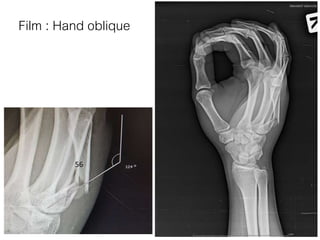

Film : Hand oblique

56

• Close fracture shaft of 5th metacarpal bone(Proximal part) of

Right hand